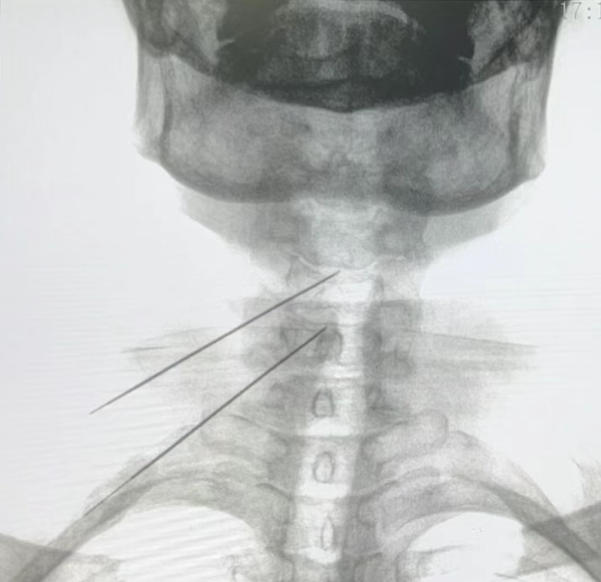

颈椎间盘射频消融联合胶原酶化学溶解术后